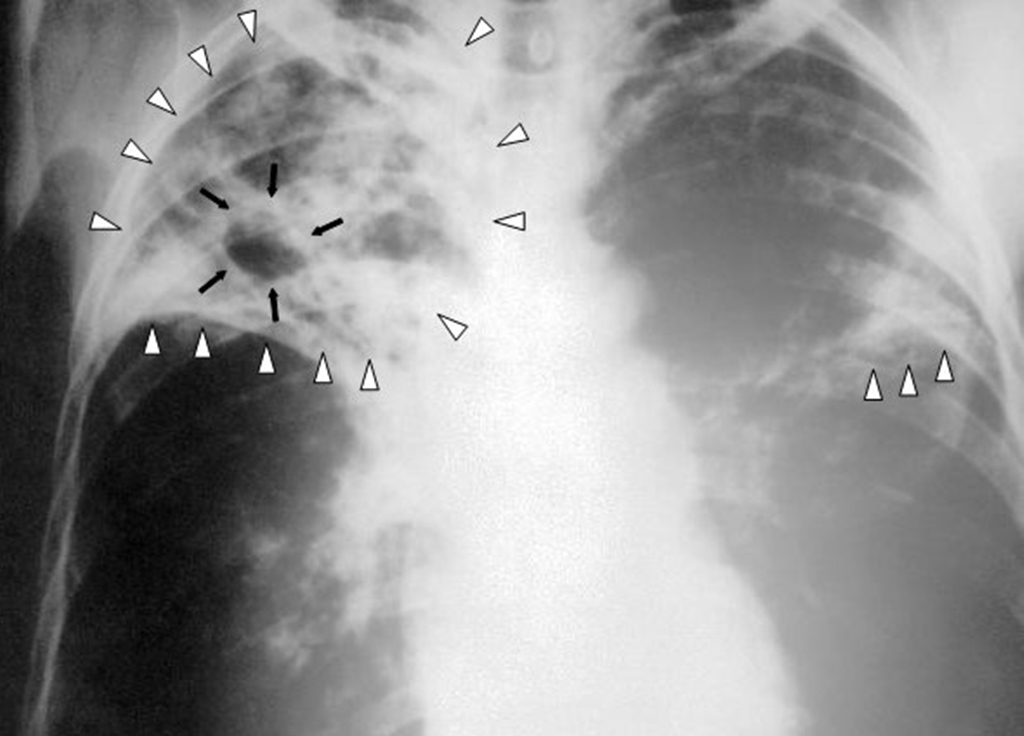

Tuberculoza, una dintre cele mai infecțioase boli din lume, este cauzată de bacterii care afectează cel mai adesea plămânii.

Se răspândește prin aer atunci când persoanele cu TBC tușesc, strănută sau scuipă. Din cauza acestei afecțiuni mor zilnic peste 4.100 de oameni, iar aproape 28.000 o dobândesc. Numărul deceselor din cauza tuberculozei a crescut în 2020, pentru prima dată în peste un deceniu, în contextul pandemiei de COVID-19.